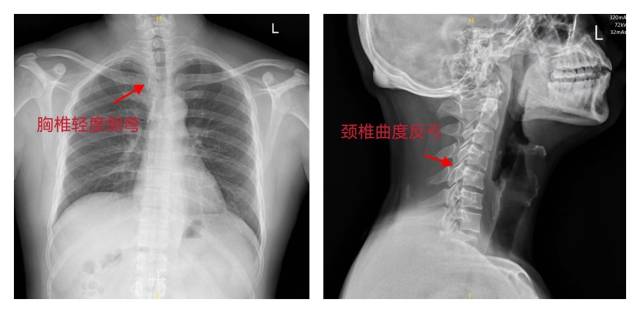

一个多月前,陈女士胸痛再次发作,痛彻后背并伴有胸闷,经人介绍来到中山大学孙逸仙纪念医院中医骨科就诊。接诊的艾亮主治医师对其进行详细查体,发现陈女士是含胸体态,后背背阔肌紧张,高低肩,胸椎4、5左侧棘突旁开2cm处有明显压痛,X光片提示颈椎曲度反弓、脊柱轻度侧弯。综合考虑,认为陈女士的胸痛症状,其实是胸椎小关节紊乱导致的感觉功能异常。

影像学资料显示胸椎轻度侧弯。